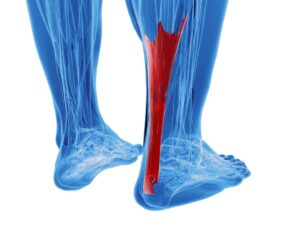

Die Orthopädie ist ein medizinisches Fachgebiet, das sich mit der Prävention, Diagnose und Behandlung von Erkrankungen und Verletzungen des Bewegungsapparates beschäftigt. Knochen, Gelenke, Muskeln, Sehnen und Bänder müssen gemeinsam funktionieren, um uns Beweglichkeit und Stabilität zu ermöglichen.

Auf unserer Seite finden Sie umfangreiche Informationen zu orthopädischen Beschwerden und Erkrankungen. Von der Arthrose über Bandscheibenvorfälle bis hin zu Kreuzbandriss und weiteren Sportverletzungen: wir geben Ihnen einen Überblick über die häufigsten orthopädischen Krankheitsbilder, wie sie behandelt werden können und inwieweit ein Bildgebungsverfahren, wie eine (z.B. MRT Knie, Rücken MRT) bei der Diagnose bei der Diagnose unterstützend wirken können.